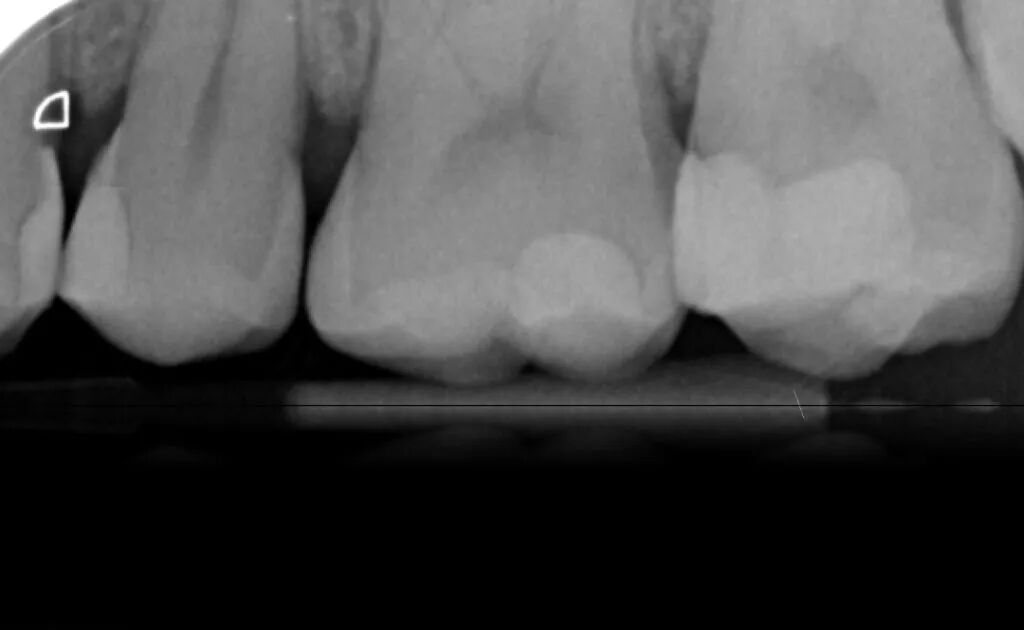

图18. 术后X线片。

总结Ionosit Baseliner可以被用作复合树脂修复的垫底材料,其被设计为一种树脂填料可以补偿聚合收缩,减少边缘缝隙和术后敏感。抵消复合树脂充填的聚合收缩是其最突出的优点,另外也能预防边缘缝隙的形成。当有缝隙存在于充填物和牙齿之间时,细菌的进入会导致继发龋的发生。Ionosit Baseliner与牙本质反应,封闭牙本质小管,防止缝隙的形成,保护牙髓免受外源性刺激。其还具有阻射性,可在X线片上观察到,并释放氟化物,起到防蛀作用。此外,其中锌成分具有抗菌性能,有助于预防继发龋。总的来说,Ionosit Baseliner是一种可靠耐用的材料,有助于无应力和持久的复合树脂修复。